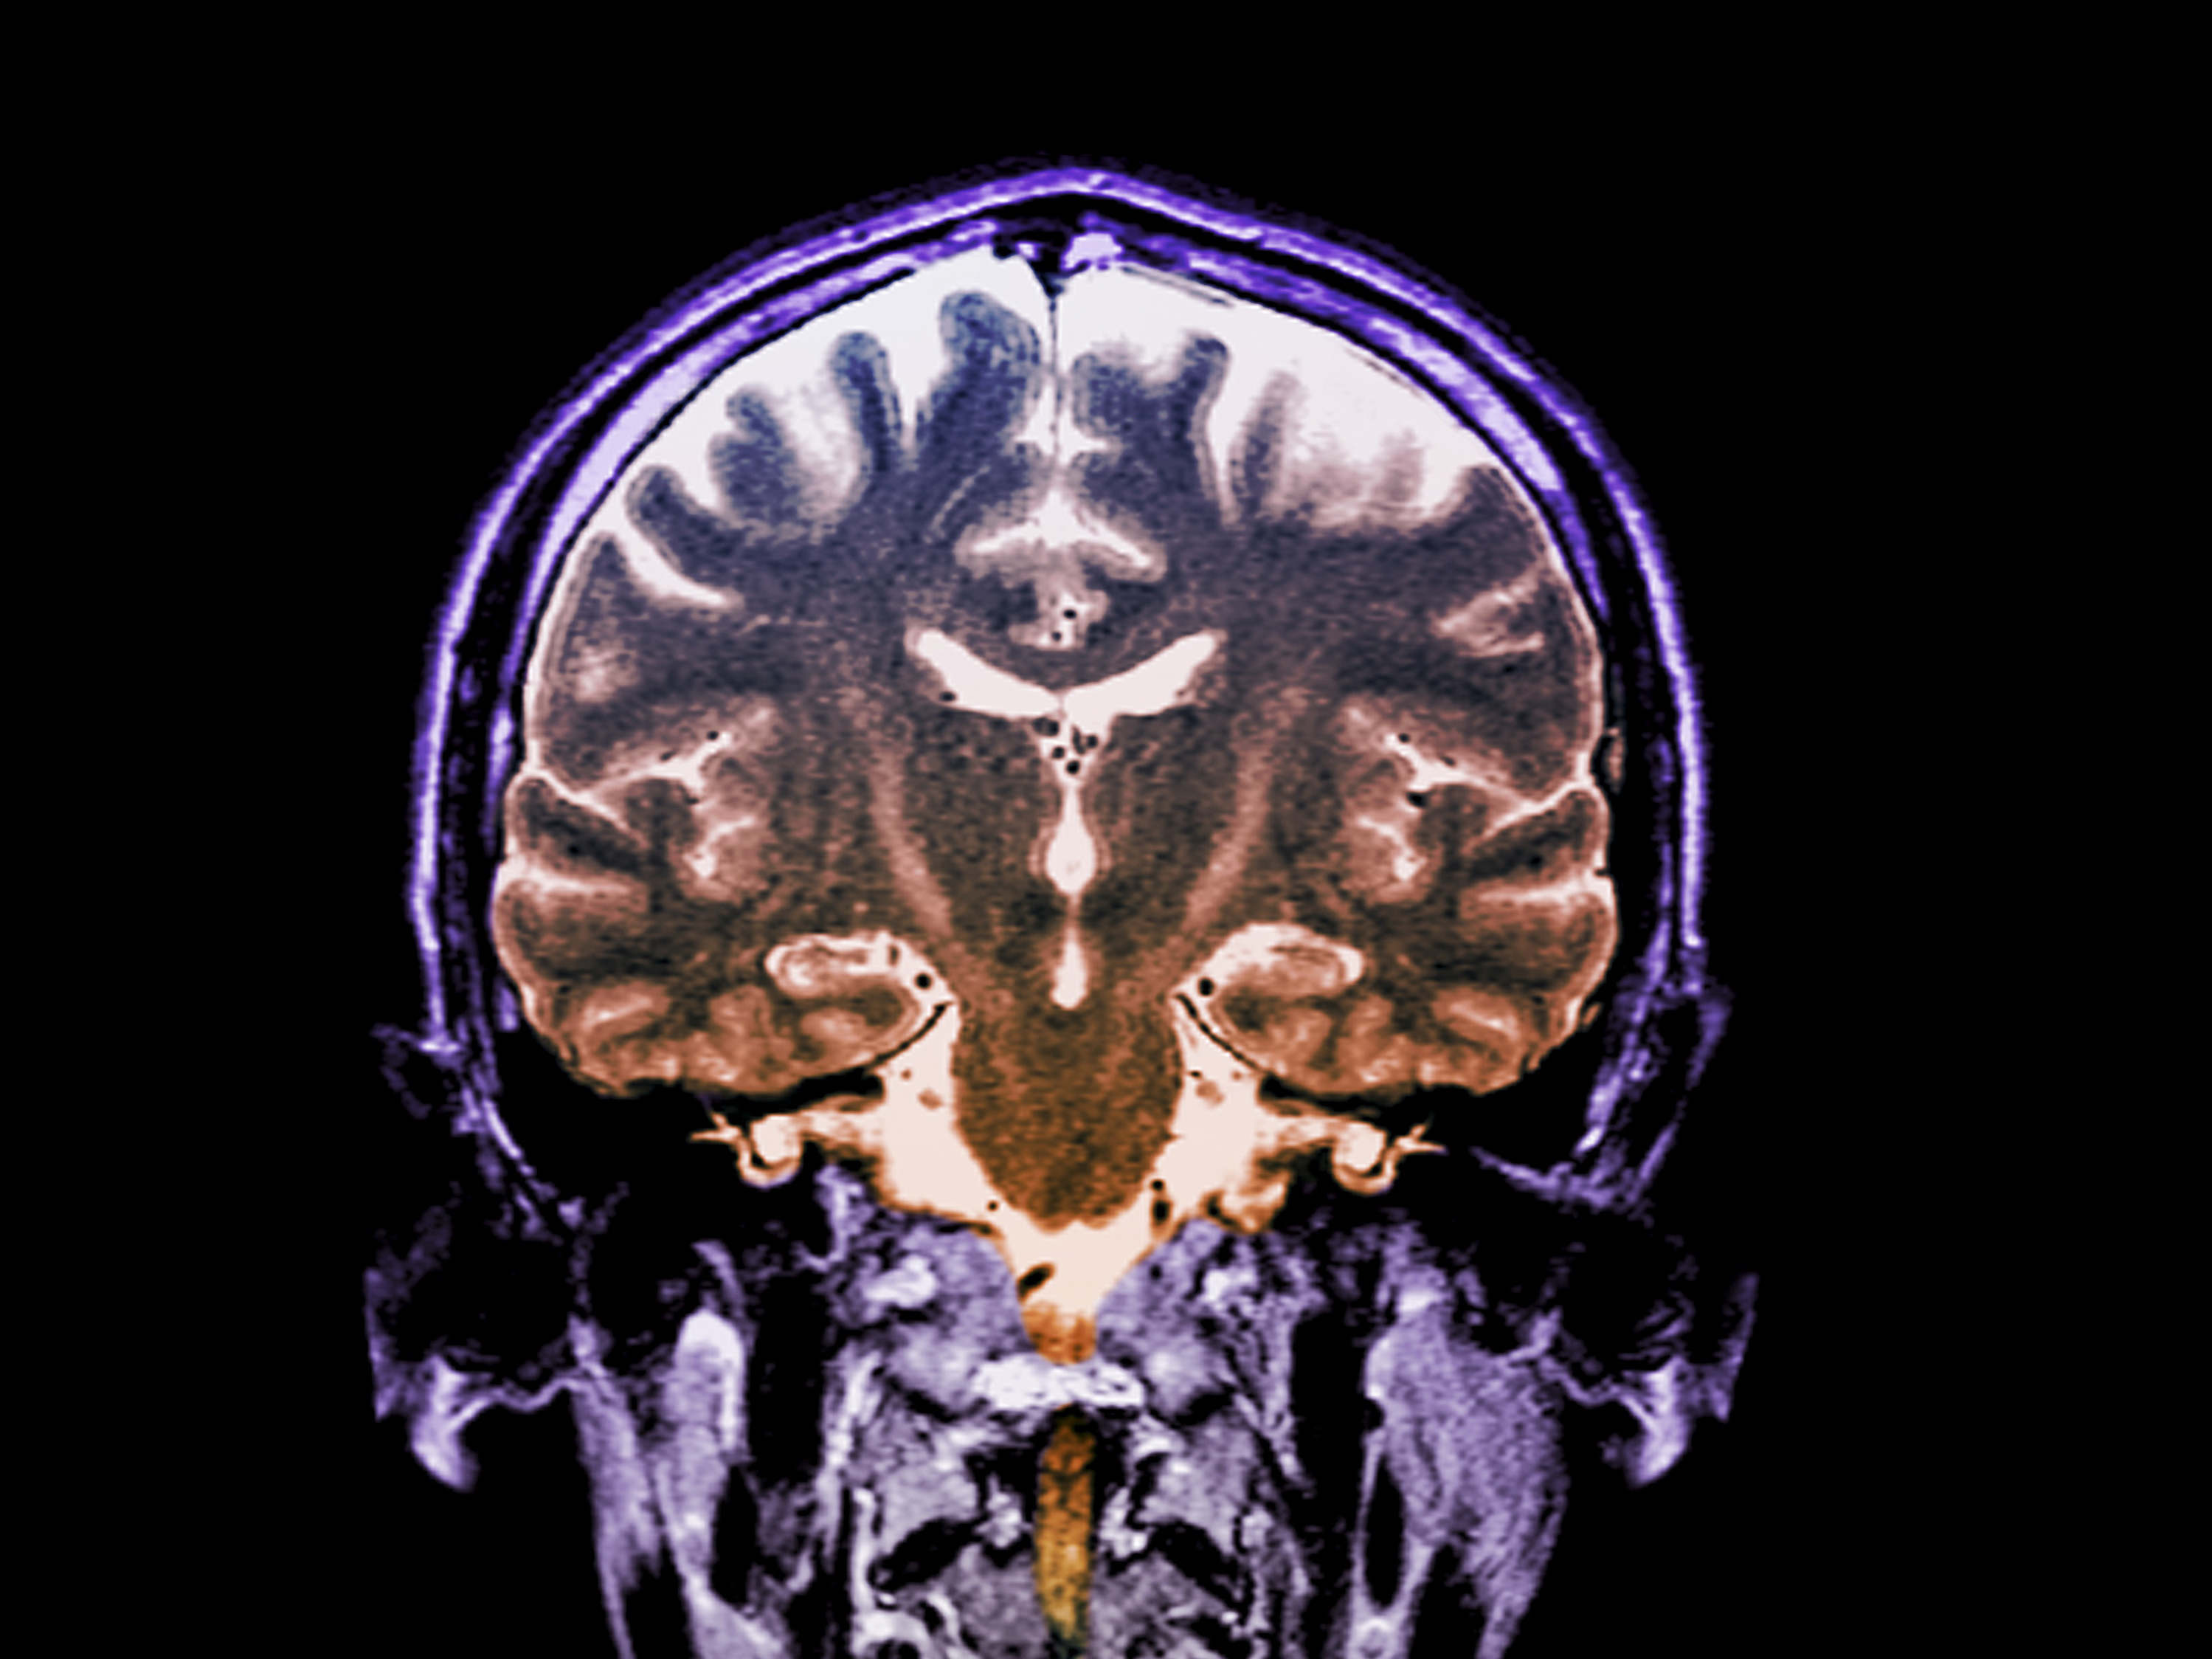

Patients with a fast-progressing form of ALS who got daily doses of an experimental two-drug combination called AMX0035 scored higher on a standard measure of function than patients who didn't get the drug. (Zephyr/Science Source)